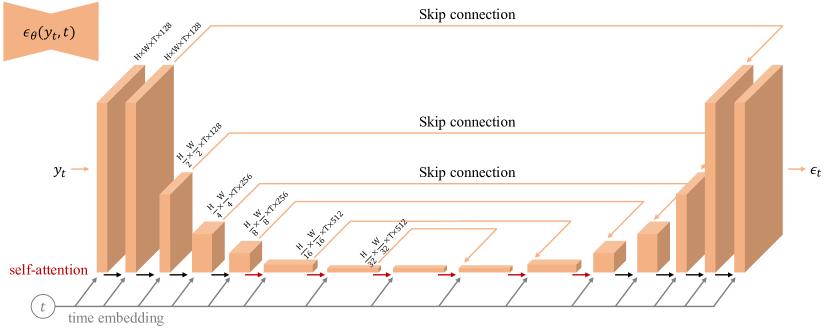

where denotes the noise prediction model using a CNN, for example, a U-Net [41, 42]. To capture the spatiotemporal features of the dynamic data, we applied 3D convolutional layers (i.e., 2D spatial + 1D temporal) in a 3D U-Net (Supporting Information Figure 6) to extract both intra-frame and inter-frame information, enabling the model to exploit the underlying spatial-temporal coherence of the data for more effective noise removal. Additionally, like DiMo [47], data consistency (DC) is incorporated into estimating , where a linear combination of partially scanned data is added to to ensure data fidelity.

Figure S6. 3D U-Net architecture used for the noise estimation network . The input has dimensions (H, W, T, 2C), where H and W represent the spatial height and width, T denotes the number of time frames, and C corresponds to the number of coils, with real and imaginary components stacked. The network employs 3D convolution kernels of size 333 and is designed as an encoder-decoder architecture with bottleneck blocks. Each encoder stage includes two residual blocks, with convolutional downsampling applied exclusively to the spatial dimensions (H and W), except at the final level. Corresponding decoder stages comprise three residual blocks and use 2 nearest-neighbor upsampling followed by convolutions to process inputs from the previous level. Skip connections between encoder and decoder stages ensure efficient feature propagation and preserve spatial and temporal details across the network. The model integrates “Self-Attention” modules, indicated by red arrows, to enhance global contextual understanding. Additionally, each residual block incorporates inputs from the preceding layer and time-step embeddings, providing information about the current diffusion time step.